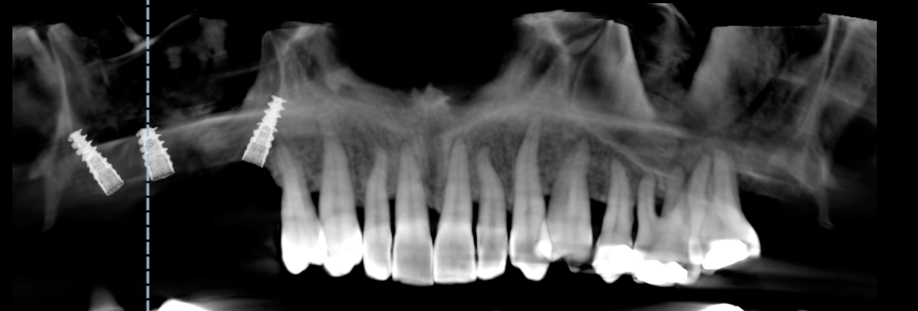

A partir de votre radio 3D réalisée au cabinet, nous lisons votre examen grace à des logiciels permettant une simulation précise du positionnement de vos implants dans l’os.

Cette vision 3D de l’implant dans l’os et en rapport avec les futures dents permet une reflexion « graftless », c’est a dire une implantologie nécessitant un minimum de greffe osseuse, donc plus rapide et moins mutilante.